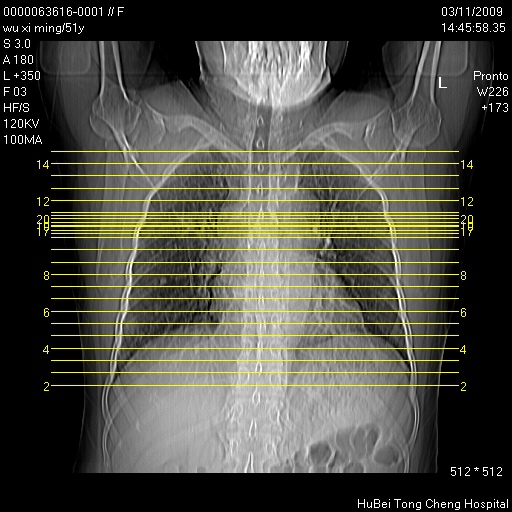

患者 女,51岁。因“胆囊炎,胆囊结石”,行常规术前胸部x线检查发现:右上肺结节病灶,建议行进一步检查。患者无咳嗽、咳痰及咯血等呼吸道症状,近期出现背部疼痛不适。

胸部ct轴位平扫(层厚10mm,螺距1.5,重建间隔10mm;部分层面:层厚3mm,螺距1.0,重建间隔3mm),图像如下: